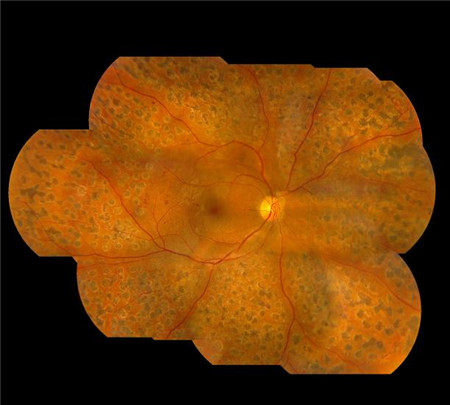

糖尿病人:我的視力這么好,為啥還要檢查眼底呢?

很多糖尿病人在聽到醫(yī)生讓自己檢查眼底時,內(nèi)心是十分困惑的:我視力還這么好,眼底怎么會有問題呢?或者,當(dāng)醫(yī)生告知自己視網(wǎng)膜已經(jīng)發(fā)生病變需要治療時,依舊不解:我穿針線都很靈活,視網(wǎng)膜還能有問題?

實際上,視網(wǎng)膜病變并不等于視力下降,這是因為在大多數(shù)情況下,視網(wǎng)膜病變初期并不會出現(xiàn)明顯的視力變化。若是等到出現(xiàn)視物模糊、眼底出血等明顯癥狀時,這個時候就已經(jīng)非常危險了。

要知道,長期的異常血糖狀態(tài)會破壞視網(wǎng)膜上的微絲血管,引起視網(wǎng)膜微絲血管病變,而發(fā)生視網(wǎng)膜脫落、黃斑水腫以及玻璃體出血這三種形式的視網(wǎng)膜病變。

不過在早期時,視網(wǎng)膜發(fā)生病變的位置可能并非位于視網(wǎng)膜中心,對視力的影響不大。而當(dāng)視力發(fā)生明顯下降時,這個時候往往已經(jīng)到了中晚期,治療的難度也大大增加。所以,人們常說:糖尿病不可怕,怕的是糖尿病引起的并發(fā)癥。

那么,面對可怕的糖尿病視網(wǎng)膜病變,糖尿病患者應(yīng)該怎么辦呢??,斞劭平ㄗh,每個糖尿病患者除了需要控制好血糖,還應(yīng)做到:不管視力是否下降,每年都應(yīng)該至少做一次眼底檢查,爭取能夠早發(fā)現(xiàn)、早治療。